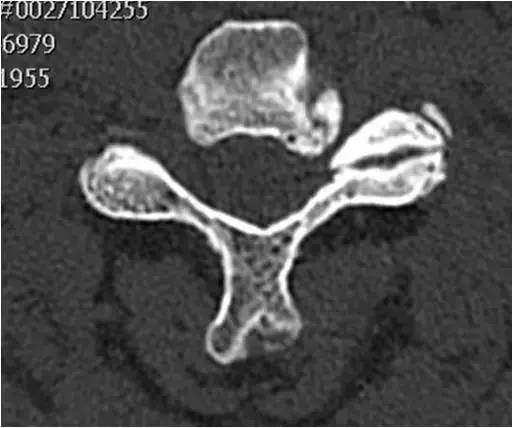

图21:颈椎中段的轴向截面。广泛的左钩椎关节肥大。左神经孔狭窄,出口神经根受压。

图22:颈椎中段的轴向截面。骨窗。与图像21相同的患者和相同的水平。广泛的左钩椎关节肥大。左神经孔狭窄,出口神经根受压。